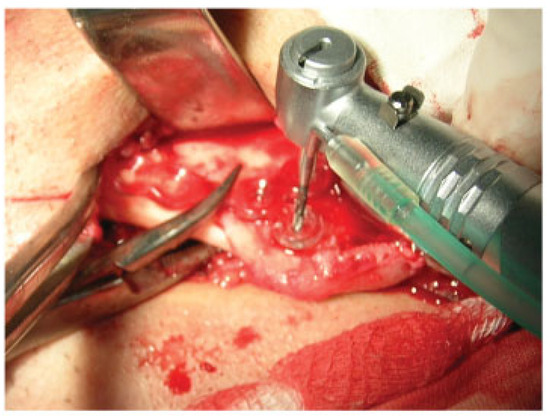

The clinical study was performed at the Department of Oral and Maxillofacial Surgery, Lviv National Medical University, Ukraine, between 2006 to 2010 and included 90 patients with 139 uniand bilateral mandibular fractures of different locations (28 condylar fractures, 88 angle fractures, 15 mental and body fractures, eight symphyseal fractures) treated surgically using HMWPE plates of our own construction and titanium screws (Synthes®, Solothurn, Switzerland; Conmet®, Moscow, Russia Federation) for their fixation. The age of the patients ranged from 18 to 65 years with a mean of 27 years. The indications for osteosynthesis were total or subtotal adentia, considerable displacement of bone fragments, ineffective conservative methods, and patient refusal for prolonged maxillomandibular fixation (MMF). Typical surgical protocol included extraor intraoral exposure of the fracture site (Figure 2) under general or local anesthesia, anatomical reduction of bone fragments (Figure 3), adaptation of the miniplate, drilling of the screw holes depending on preferred monoor bicortical insertion (Figure 4), fixation of the mini-plate with titanium screws (Figure 5), and suturing of the wound. Patients were administered analgesic antibiotics for 5 to 7 days in routine dosages as well as antiseptic solution for regular mouthwash. All patients were observed clinically for 12 to 16 months postoperatively with a mean of 14 months.

Figure 4. Typical surgical protocol. Adaptation of the miniplate, drilling of the screw holes.